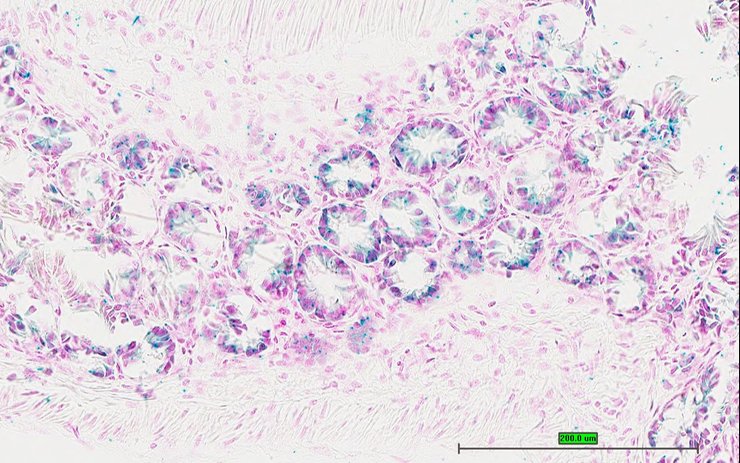

TS28: lung Present UC Davis_1880053

TS28: lung Present UC Davis_1880070

Structure Level Pattern Image Note

TS28: lung Present UC Davis_1880071